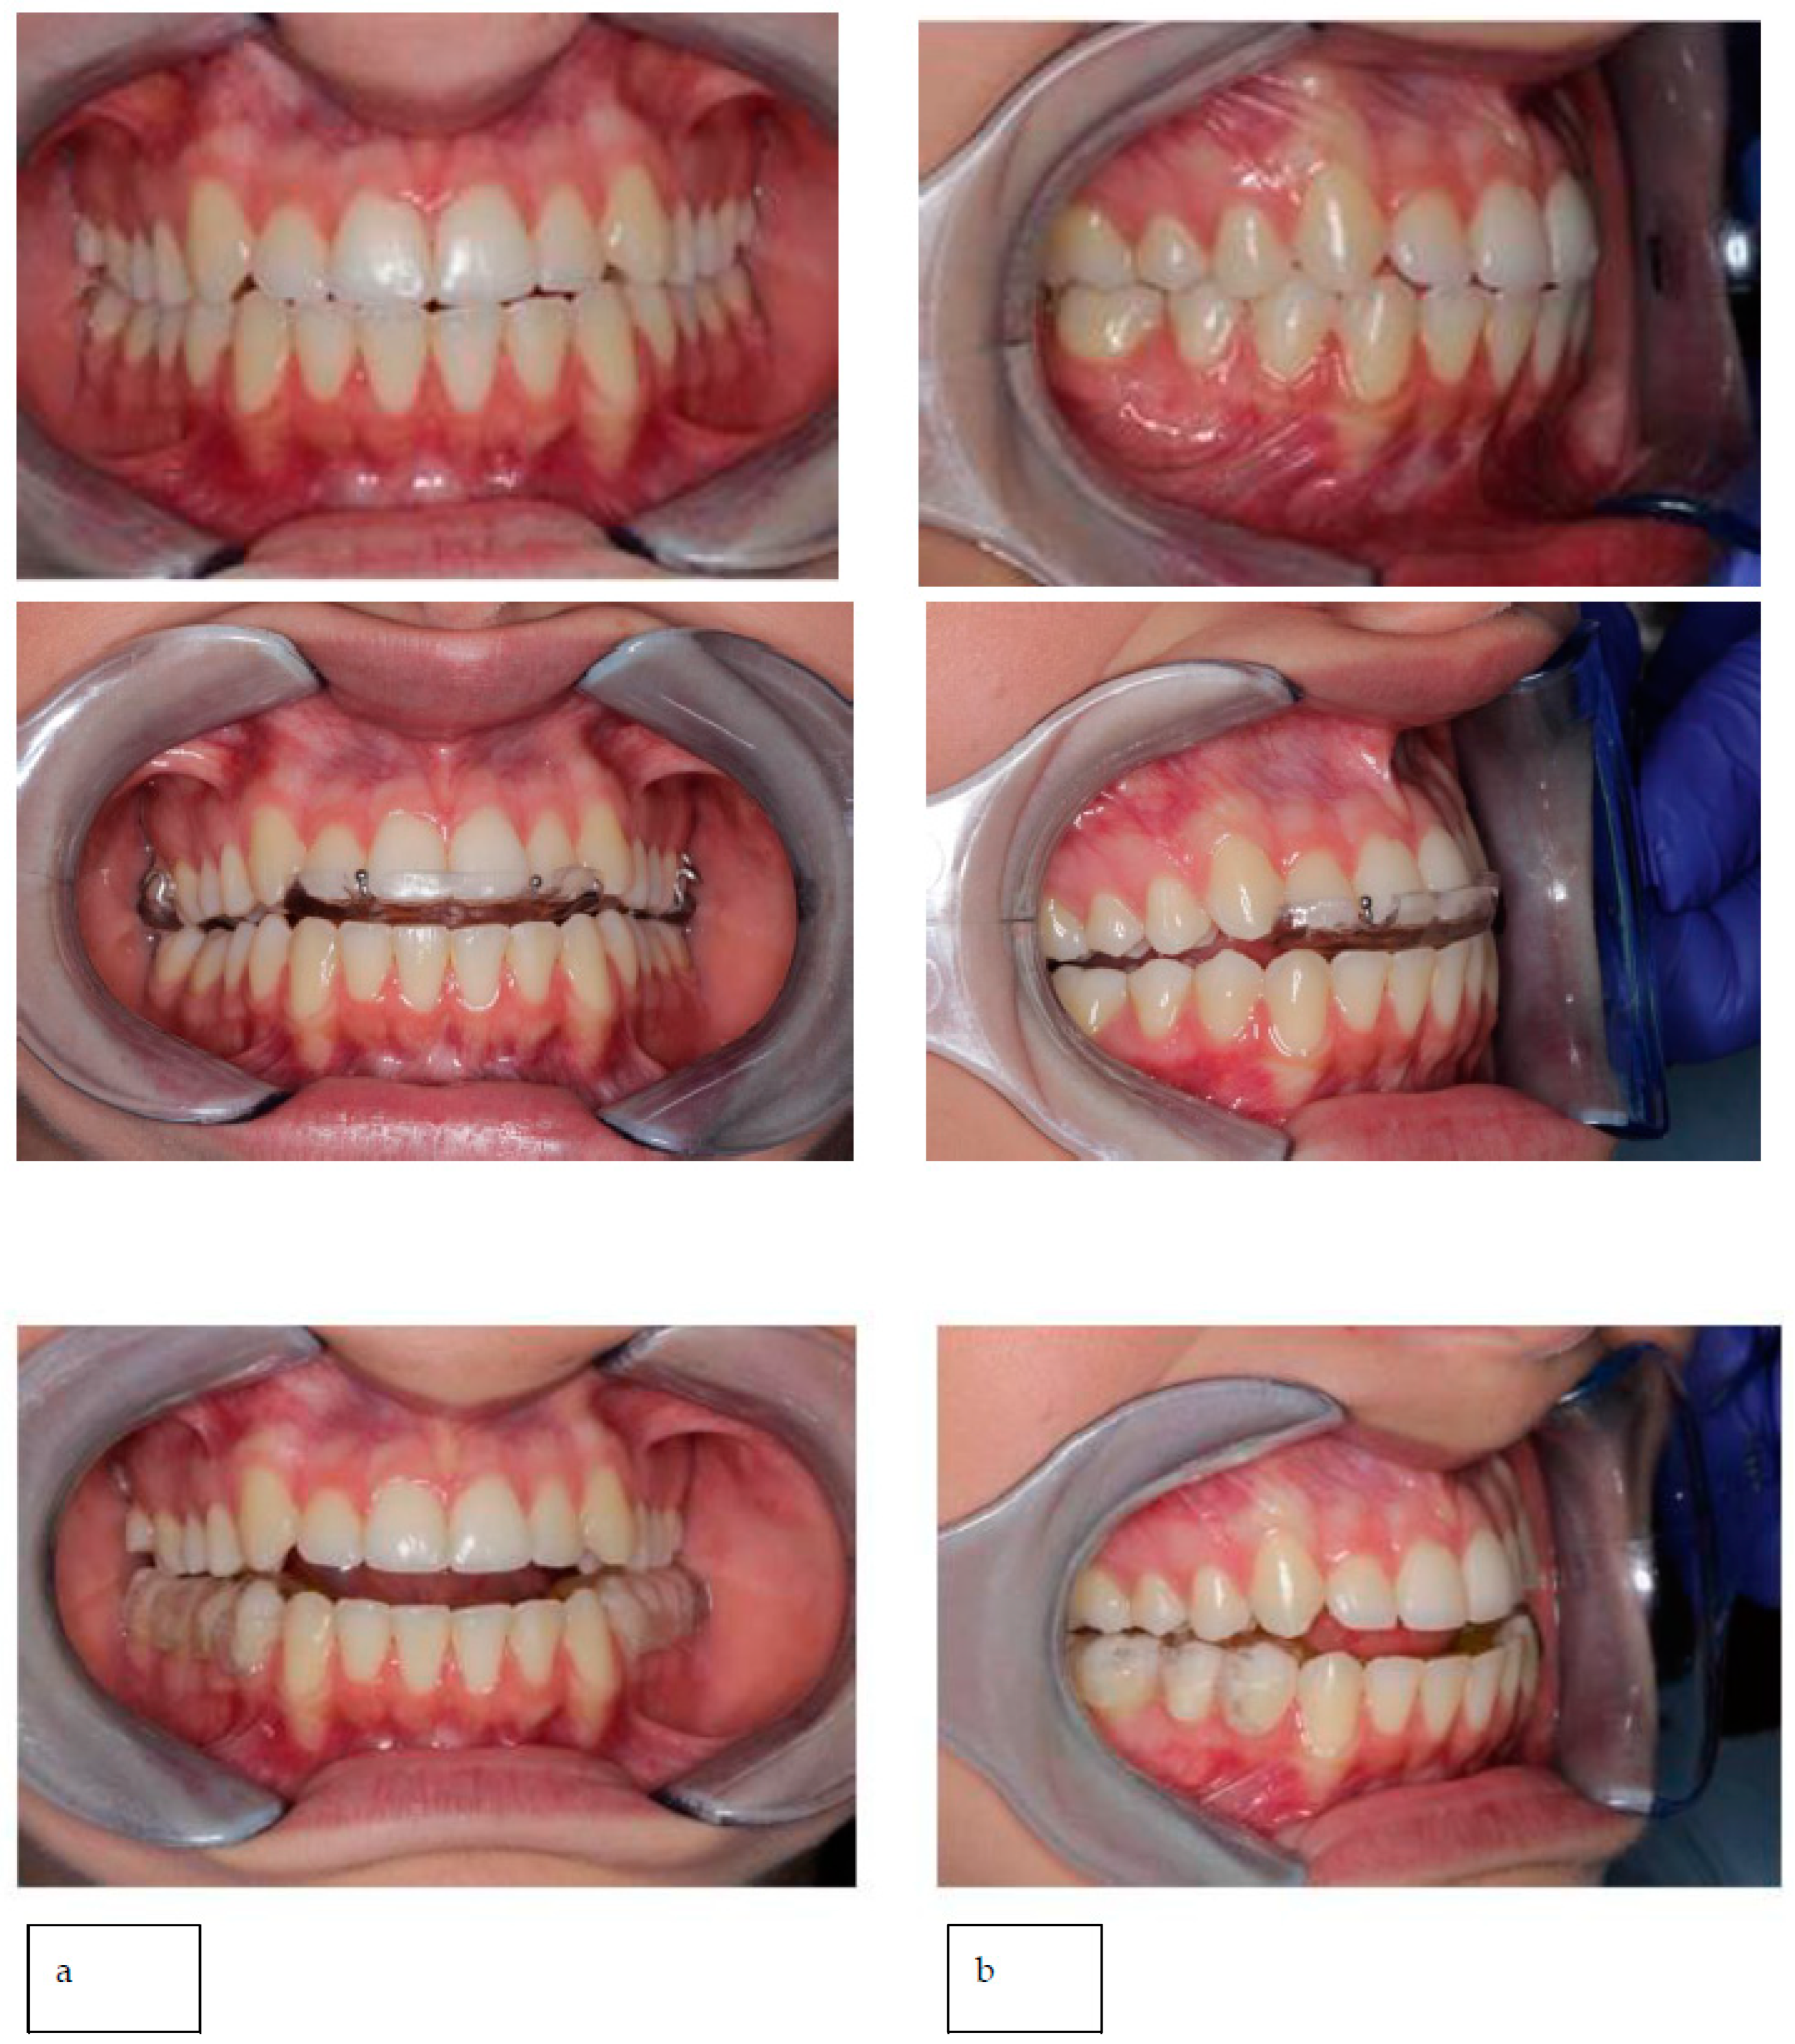

Intraoral occlusal relationships are shown in Figure 16.

Figure 16. Intraoral photos and intraoral scans show occlusal relationships: class I molar on the right and left and lower midline deviated to the right compared with the upper.